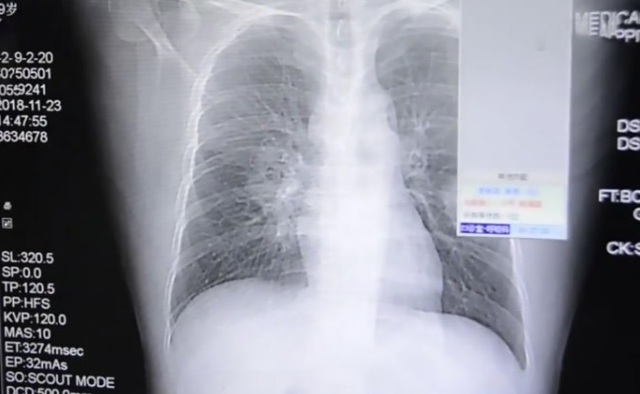

【로스앤젤레스=뉴시스】 퇴근 후 집에 돌아와 하루 종일 신고 있던 양말의 냄새를 맡는 습관을 갖고 있던 중국 남성이 곰팡이균으로 인한 폐질환에 걸렸다고 영국의 데일리 메일이 19일(현지시간) 중국 푸젠(福建) 지역언론을 인용해 보도했다. 이유를 모른 채 가슴통증으로 병원을 찾았던 37세 중국 남성의 가슴 엑스레이 사진 <사진출처=Pear Video> 2018.12.19

‘펑’이라는 성(姓)만 알려진 이 남성은 어느 날 가슴이 조이는 듯한 통증과 기침이 심해져 병원을 찾았다.

의료진은 다시 검사한 결과 환자의 폐가 심각한 곰팡이균에 감염돼 있음을 발견했다. 환자를 진료했던 장저우 909병원의 마이 주아닝 의사는 지역언론 복건일보(福建日報)와의 인터뷰에서 “환자가 평소 휴식 부족으로 면역력이 약화돼 곰팡이균에 쉽게 감염됐을 것으로 판단된다”고 말했다.